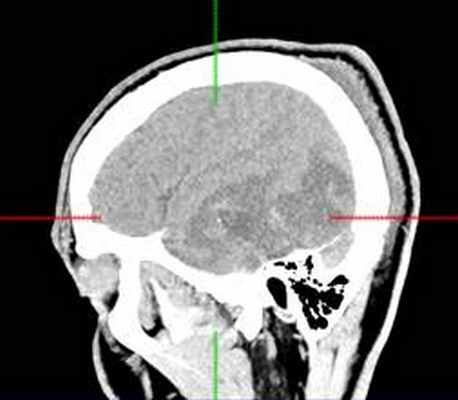

КТ головного мозга с контрастным усилением (24.03.2015): объемное кистозно-солидное образование правой теменно-височно-лобной области. Дислокационный синдром.

22.10.2015 была выполнена операция: микрохирургическое удаление опухоли правой височной доли под интраоперационными навигационным контролем и с интраоперационной фотодинамической терапией.

КТ головного мозга (23.10.2015): не выявило признаков кровоизлияния или каких-либо других хирургических осложнений в области оперативного вмешательства.